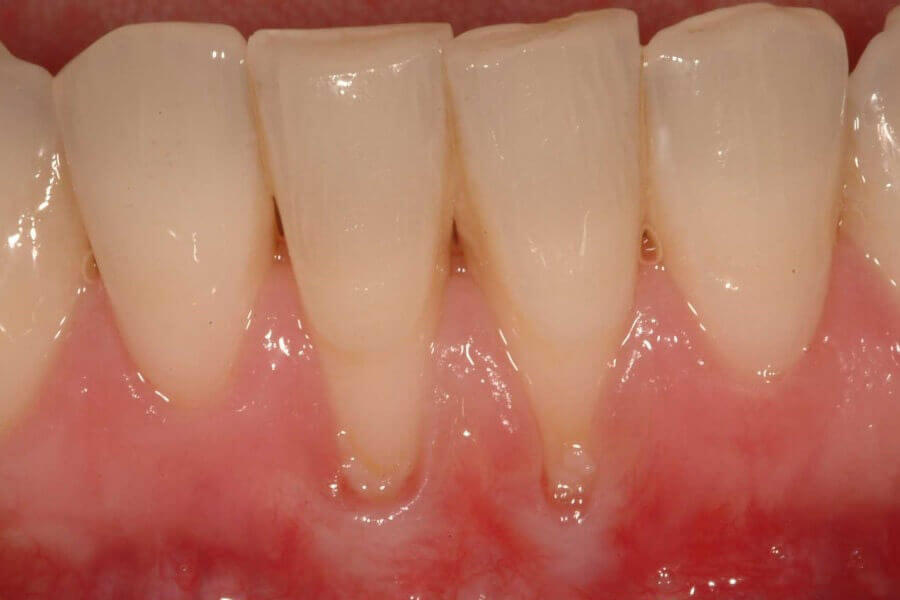

Пародонтоз провоцирует развитие дистрофии десен, появление раздражения на слизистой оболочке рта. Основными симптомами, свидетельствующими о начале развития у ребенка заболевания, являются

- Ощущения пошатывания зуба и оголение его шейки, появление клиновидного эффекта;

- Стертость зубной эмали и бледный цвет десен.